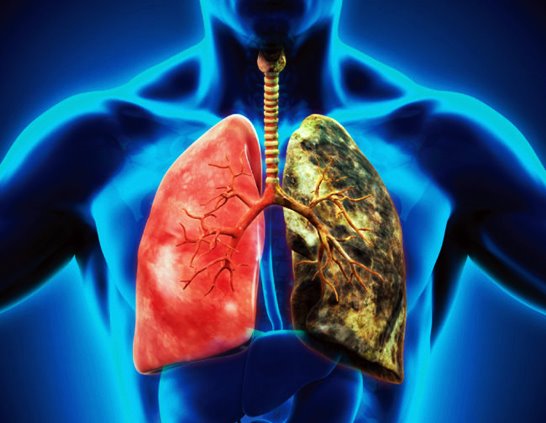

흡연은 폐암의 가장 큰 원인 중 하나입니다. 담배를 피우지 않거나 금연하는 것이 폐암 예방에 가장 효과적입니다. 만약 흡연 중이라면 의사나 금연 전문가의 도움을 받아 금연 계획을 수립하는 것이 좋습니다.